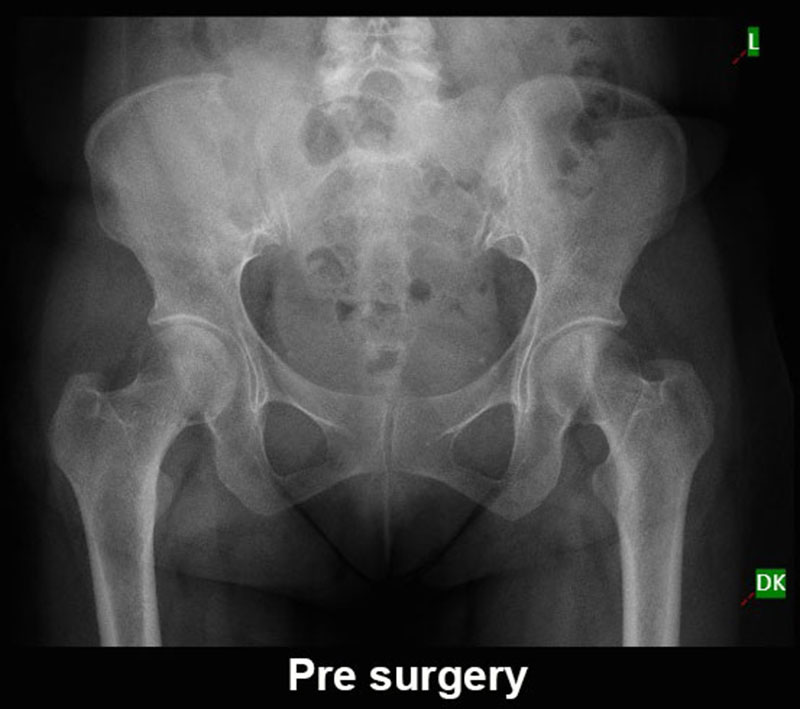

ಕೆಎಂಸಿ ವೈದ್ಯರ ಯಶಸ್ವಿ ಸಾಧನೆ: ಕಾಲು ಉಳಿಸುವ ಯಶಸ್ವಿ ಕ್ಯಾನ್ಸರ್ ಶಸ್ತ್ರಚಿಕಿತ್ಸೆ